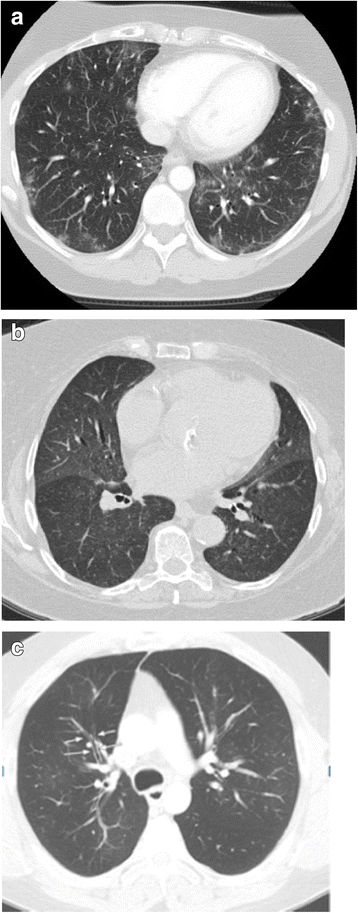

Rituximab toxicities can manifest on imaging (Figs. 4 and 5). Notably, lung toxicities in the form of interstitial pneumonitis and acute respiratory distress syndrome (ARDS) have been well-described, and although they are rare, they can be life threatening [27,28,29]. Three time-to-onset patterns have been described: ARDS within hours of first infusion, acute/subacute hypoxemic organizing pneumonia within 2 weeks of last infusion, and macronodular organizing pneumonia with insidious/longer onset [27]. On high resolution computed tomography (HRCT), findings include focal or diffuse ground glass opacities and consolidation (Fig. 4) [28]. Rituximab is also known to increase the risk of hepatitis B reactivation in carriers, which can result in acute liver injury, andmanifestson CT with decreased liver attenuation, gallbladder wall edema > 3 mm and mild periportal edema [30]. Progressive multifocal leukoencephalopathy (PML) has also been reported in rituximab-treated CLL patients, which is a rare demyelinating condition caused by JC virus reactivation [31]. On brain MRI, PMLmanifests as FLAIR hyperintense white matter lesions.

Spectrum of lung toxicities caused by Rituximab. a Axial CT images of the chest acquired during arterial phase in a 48-year-old female patient with CLL on maintenance therapy with Rituximab show bilateral ground glass opacities more prominent in the left lower lobe suggestive of drug induced pneumonitis. b Axial CT images of the chest in an 84 year old female patient with CLL on Rituximab therapy shows bilateral, symmetric homogenous ground glass opacities in both the lungs consistent with hypersensitivity pneumonitis c Axial CT images of the chest obtained during arterial phase in a 45 year old male patient with CLL on maintenance with Rituximab shows hypoattenuated lungs with peribronchial thickening suggestive of bronchiolitis obliterans (thin white arrows)